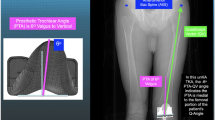

3D reconstructed patient femora and tibiae were generated using the imaging software ScanIP (Simpleware, Exeter UK) from pre-operative CT scans [6]. Landmarks describing bone and soft-tissue references are identified by trained engineers qualified by the lead study author used to define patient-specific bone axes and soft-tissue attachment sites [22, 26]. The pre-operative models and landmarks were registered to the post-operative CT scan. In addition, 3D implant models of the implanted components were also registered to the post-operative CT scan. This whole process has been previously shown in a validation study to produce maximum errors of 0.9° ± 0.6° and 0.5 mm ± 0.3 mm with an intra-class correlation coefficient (ICC) > 0.93 indicating excellent reliability [28]. These models, landmarks and component positions were used to produce a computational simulation (see Fig. 1). The simulation replicates a deep knee bend performed in an Oxford Knee Rig (OKR), and includes modelled collateral ligaments, a quadriceps tendon and other passive soft-tissue restraints. All ligaments were modelled as one or two bundles of nonlinear springs as described by Abdul-Rahman et al. [1] with fixed parameters further adapted using a process previously described by Theodore et al. [22, 23, 26]. In this way, the model captures the combination of patient-specific elements, component geometry and component position and orientation that contribute to the dynamic joint motion.

DKS model performance was evaluated with a counter-factual study design. First, the achieved surgical result and implant position was simulated. Then, a set of alternate surgical plans the surgeon might have followed were simulated. From each simulation, the DKS score is generated, giving a score from 0 to 100 that predicts the probability of a Patient Acceptable Symptom State (PASS) being reached, using cut off values [12] and via a process described in a previous publication [23]. Patients were grouped by whether (a) the surgically achieved position scored the highest DKS of the variants or (b) whether an alternative simulation scored higher, which would indicate an alternate approach to the surgery was predicted to be more likely to reach a PASS outcome (Fig. 2).

The alternate simulation sets used to cover other surgical plans covered (a) altered posterior resections (+3 mm to – 3 mm resection in 1mm increments), (b) altered tibial slopes (0–12 degrees in 3-degree increments) and (c) altered femoral rotation (matched to the Posterior Condylar Axis (PCA) or matched to the surgical Transepiconylar Axis (TEA)). This gives a total of 13 simulations per patient, which combined with their simulation of actual surgically achieved position amounts to 14 simulations per patient. Evaluation questions were compiled from the KOOS questionnaire to investigate for a relationship to the specific simulated kinematic response expected from the investigated component alignment change. For slope and posterior resection, the following three questions relating to Range of Motion (ROM) were evaluated: “Can you straighten your knee fully?”, “Can you bend your knee fully?”, “Do you experience difficulty descending stairs?”. For femoral rotation, responses to three questions focused on patellar function were evaluated: “Does your knee catch or hang up when moving?”, “Do you feel grinding, hear click or any other type of noise when your knee moves?” and “Do you experience difficulty squatting?”.